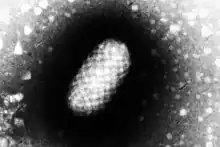

![]() | |

Virus classification ![]() | |

(unranked): | Virus |

Realm: | Varidnaviria |

Kingdom: | Bamfordvirae |

Phylum: | Nucleocytoviricota |

Class: | Pokkesviricetes |

Order: | Chitovirales |

Family: | Poxviridae |

Genus: | Parapoxvirus |

Species: | Orf virus |